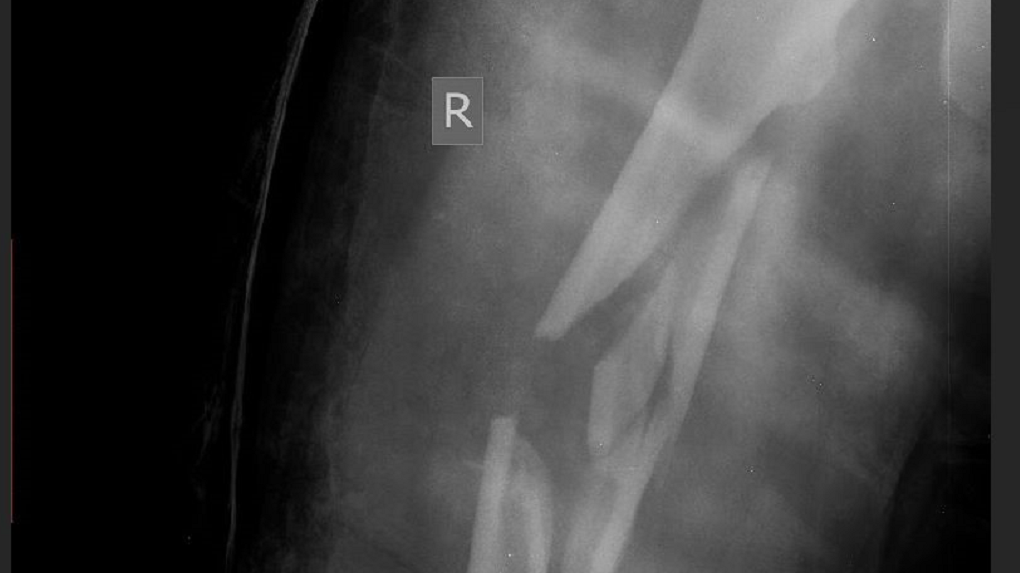

Хирурги омской БСМП-1 помогли пациентке со сложным переломом. Бедренную кость девушки, попавшей в аварию, ударом раздробило на 12 фрагментов — травматологи провели большую работу по её восстановлению. «Собирали, как пазл», — рассказывают в клинике.

Олег Козарь, заведующий отделением травматологии БСМП-1, рассказал порталу Om1.ru, как проходила операция: «Вся средняя часть бедра была раздроблена. Фрагменты скрепляли между собой винтами, фиксировали проволокой. Чтобы осколки заново правильно срослись, в кость пациентке вставили металлический стержень, на котором и держалась вся конструкция. Для нас важно было сделать все так, чтобы молодая совсем девчонка не осталась инвалидом и ушла от нас на своих ногах».